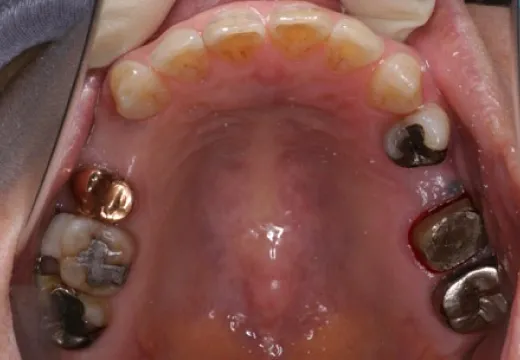

治療例

ホームページをご覧の皆さまにできる限り分かりやすいように、術前・術中・術後の治療例をご紹介いたします。ご参考になれば幸いです。

術前咬合面

術後咬合面